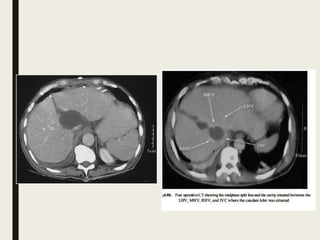

Dodds et al. AJR 1989

Dodds et al.AJR 1989